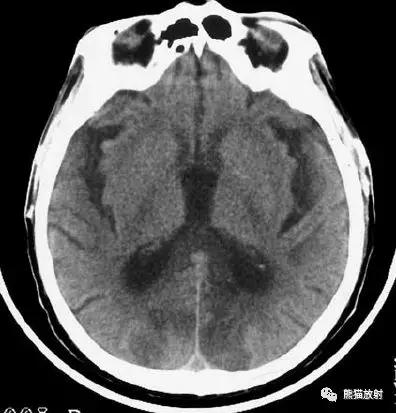

右侧豆状核梗死灶(发病后15d),明显均匀强化。另左侧丘脑见腔隙性梗死灶。

左侧大脑中动脉区域大面积梗死,明显不均质强化。

右侧大脑中动脉区域脑梗死,脑回样强化。

左侧额叶脑梗死(发病后12d),由于模糊效应平扫显示不清,增强扫描脑回样强化。

右侧基底节区脑梗死,增强后病灶看上去有所缩小。